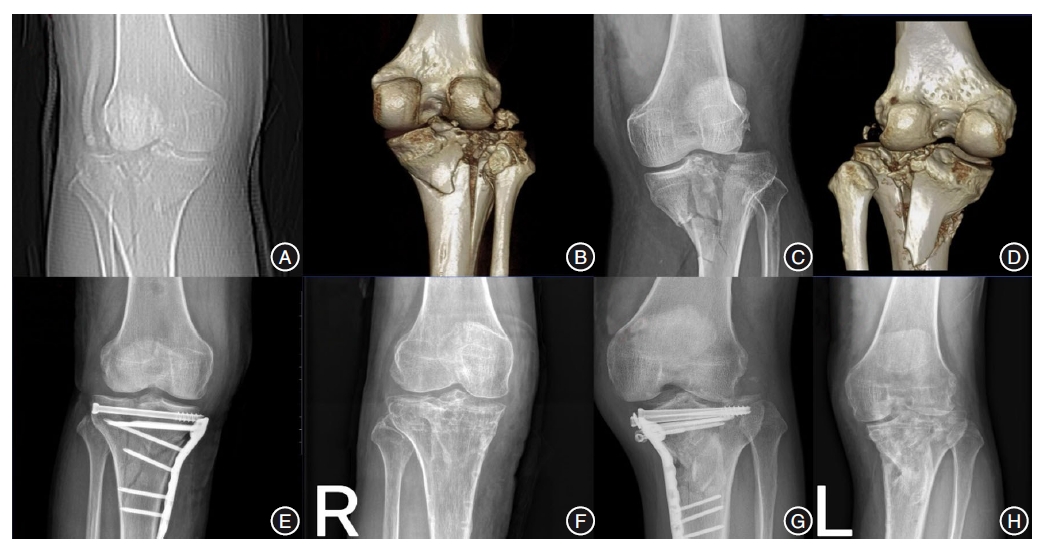

目的 测量X线下胫骨平台与股骨远端的解剖学关系,并评估Schatzker IV-C胫骨平台骨折术中平台宽度复位情况对术后临床疗效的影响。 方法 2012年8月至2022年8月,在我院收集207例标准中立位正常成年人膝关节X线(未骨折组)及60例Schatzker IV-C型骨折患者术前及术后即刻膝关节前后位X线(骨折组)。分别测量两组胫骨近端关节宽度(TAW)、股骨远端髁宽度(DFW)及股骨远端关节宽度(FAW),计算TAW/DFW和TAW/FAW比值,定义骨折组术后即刻X线TAW介于FAW与DFW之间为复位良好组,反之为复位不良组,并在术后1年对两组进行膝关节美国特种外科医院评分(HSS)。 结果 在未骨折组中,TAW/DFW和TAW/FAW比值无明显性别或侧别差异(P > 0.05),而骨折组术前与未骨折组TAW/DFW和TAW/FAW比值差异有统计学意义(P < 0.05)。骨折组中复位良好组与复位不良组的术后1年HSS评分比较差异有统计学意义(P < 0.05)。 结论 正常成年人胫骨平台与股骨远端的X线下解剖学关系相对恒定,可为Schatzker IV-C骨折术中平台宽度复位提供影像学参考,若术后复位后X线TAW/DFW> 1或TAW/FAW < 1提示复位不佳,则预示术后膝关节功能恢复不良。

Objective To investigate the radiographic anatomical relationship between tibial plateau and distal femur and evaluate the impact of reset tibial plateau of various widths after reduction of the Schatzker IV-C tibial plateau fractures on postoperative outcomes. Methods We collected and reviewed the X-ray images of the normal knees of 207 standard neutrally-positioned adults (non-fracture group) and pre-and post-operative immediate anterior-posterior X-ray images of the knees of 60 patients with Schatzker IV-C fractures (fracture group) in our hospital from August 2012 to August 2022. We measured the proximal tibial joint width (TAW), distal femoral width (DFW), and distal femoral joint width (FAW) in both groups and calculated the TAW/DFW and TAW/FAW ratios. In the fracture group, the cases with TAW between FAW and DFW were assigned to the well-reduced group, while those with TAW outside this range between FAW and DFW to the poorly-reduced group. Both groups were assessed using the Hospital for Special Surgery knee score (HSS) one year after operation. Results In the non-fracture group, there were no significant differences in gender or affected side in terms of TAW/DFW and TAW/FAW ratios (P > 0.05), while in the fracture group, there were statistically significant differences in the TAW/DFW and TAW/FAW ratios compared to the non-fracture group (P < 0.05). There was a statistically significant difference in the one-year postoperative HSS scores between the well-reduced and poorly-reduced groups in the fracture group (P < 0.05). Conclusion The radiographic anatomical relationship between the tibial plateau and distal femur in normal adults is relatively constant, providing a radiological reference for resetting the tibial plateau to a satisfactory width during reduction of Schatzker IV-C fractures. TAW/DFW > 1 or TAW/FAW < 1 indicates a poor reduction of the fracture and predicts poor postoperative recovery of knee joint function.